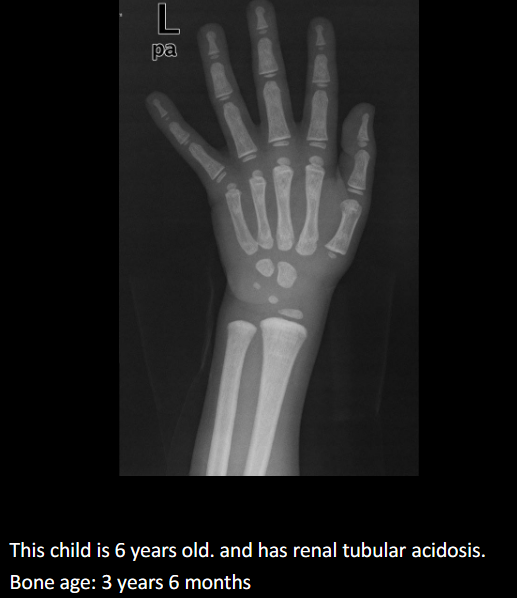

Purpose of bone age studies.

Assess growth/endocrine issues, stature, puberty timing, predict adult height.

Define delayed bone age.

2 years behind chronological age; aka CDGP.

List causes of delayed bone age.

↓ hormones; systemic (heart/urinary/digestive), chromosomal, familial short stature, idiopathic.

Typical stature in delayed bone age.

Short for age.

Standard imaging and method for bone age.

PA hand & wrist, Greulich & Pyle comparison.